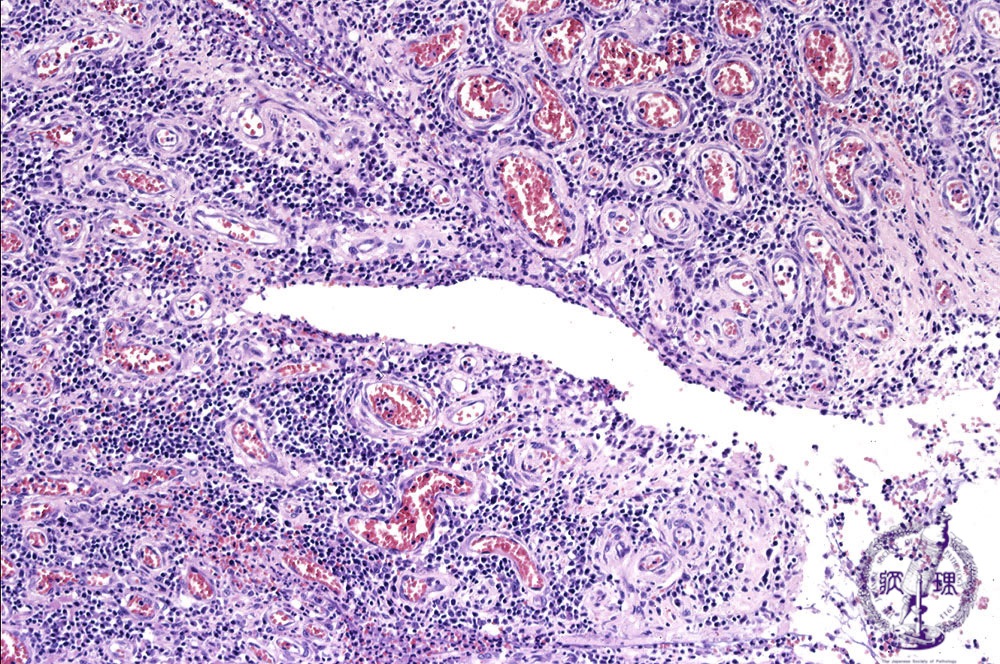

Microscopic view (H&E stain, medium power): Fissure formation is seen.